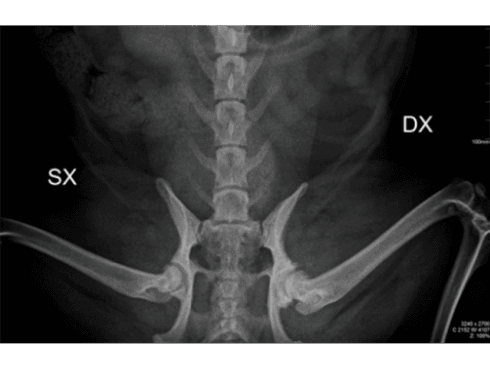

- ortopedica;

- radiografia digitale;